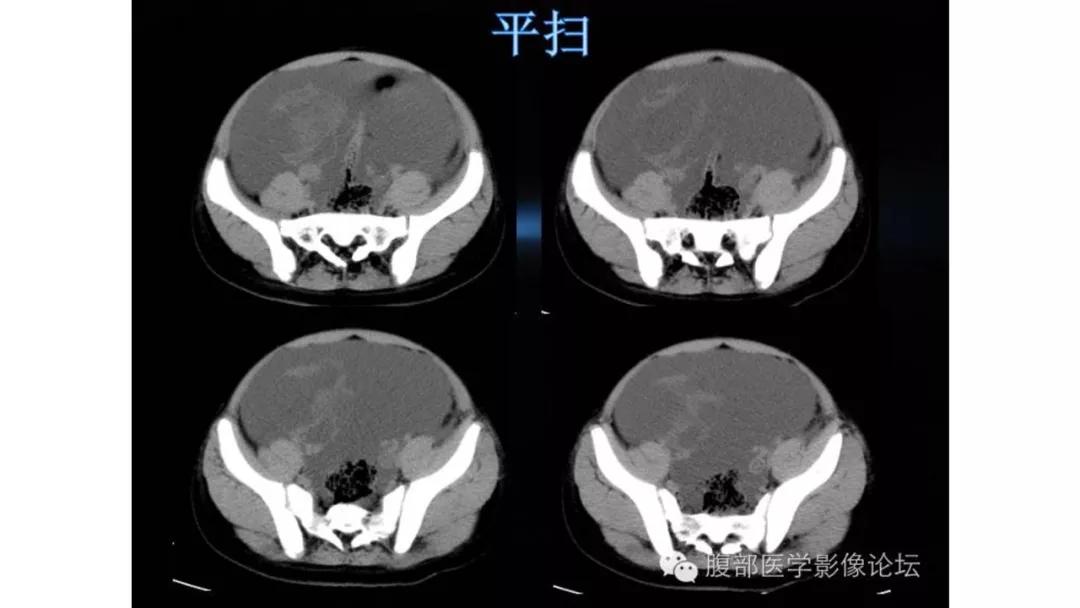

病理:颗粒细胞瘤